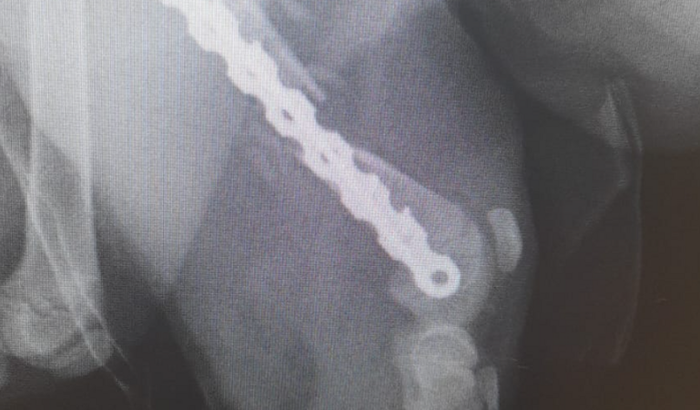

Kenai fez a cirurgia mas a placa usada na primeira cirurgia saiu do lugar e ele refez o procedimento dando mais 4 mil reais. Por favor nos ajudem!!